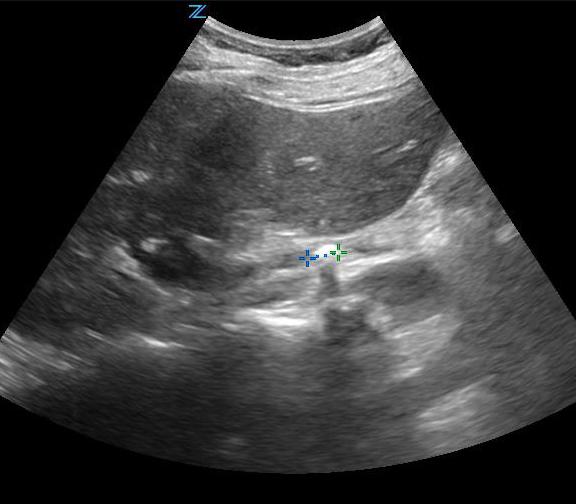

- For measuring bladder volume, use the US volume measurement feature or the formula 0.52 × Depth × Width × Height.

- In the transverse view, find the largest bladder size and measure both the vertical and horizontal length of the bladder image from inner wall to inner wall. This corresponds to the bladder depth and width, respectively.

- In the sagittal plane, measure the maximum horizontal length of the bladder image from inner wall to inner wall. This corresponds to the bladder height.

- Figures 3 and 4. Measurement of bladder volume in the transverse (Figure 3) and sagittal (Figure 4) views